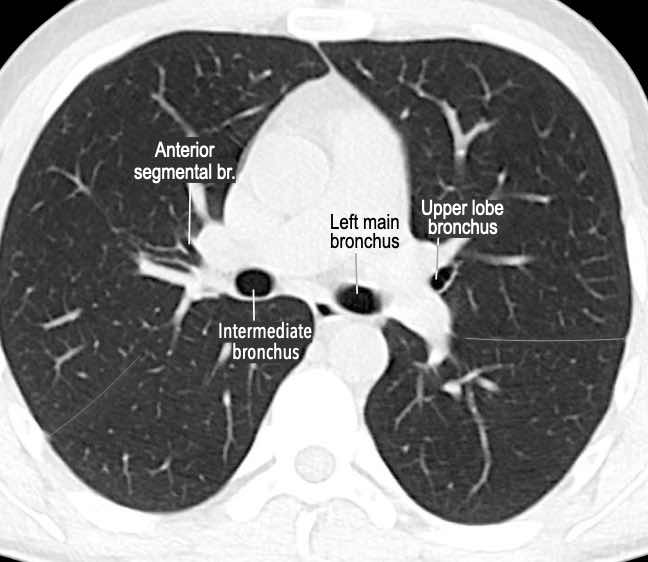

Phế quản trên CT

Cuộn qua các hình ảnh để quan sát khí quản phân chia thành phế quản chính phải và trái, sau đó tiếp tục phân chia thành các phế quản thùy và phế quản phân thùy.